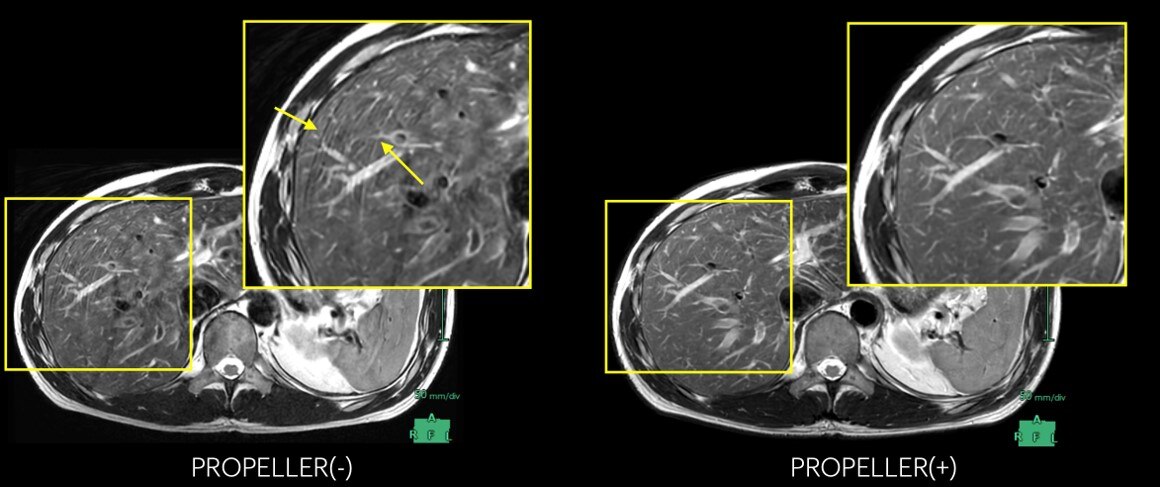

下記に商品説明や配送料・配送方法・注意事項等の説明がございます。MRI認定 43】マジックアングル | ラドライフ。アーチファクト例 - 生理的因子 | 画像診断情報サイト Bayer in。

【インボイス制度対応済み】当社では2023年10月からインボイス制度に対応した適格請求書発行事業者番号(通称:T番号・登録番号)を印字した納品書(明細書)を商品に同梱してお送りしております。こちらをご利用いただくことで、税務申告時や確定申告時に消費税額控除を受けることが可能になります。聖隷浜松病院における使用経験 Discovery MR750 を使用した躯幹。アーチファクト例 - 物理的因子 | 画像診断情報サイト Bayer in。どちらのサイトからもご購入可能です。

画像診断 12年1月号 32ー1 特集:MRIアーチファクトの光と影